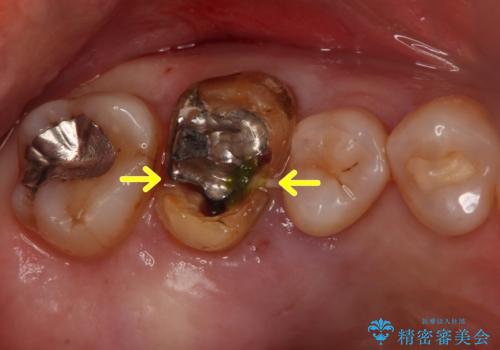

- 銀歯を白くしたいとのことで来院されました。

銀の詰め物を除去した後、その奥にある古い詰め物も除去し完全にむし歯を取り切ったことを確認してからセラミッククラウンを装着していきます。